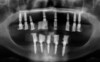

Son cliché panoramique montre de nombreuses infections dentaires et parodontales ingérables.

Le cliché panoramique montre le bon ajustage des pièces en titane et du bridge provisoire en résine armé par des fibres de verre.

Le cliché panoramique permet d’apprécier l’ajustage des armatures usinées sur les piliers et la différence de contraste radiologique entre la zircone au maxillaire et le titane à la mandibule.